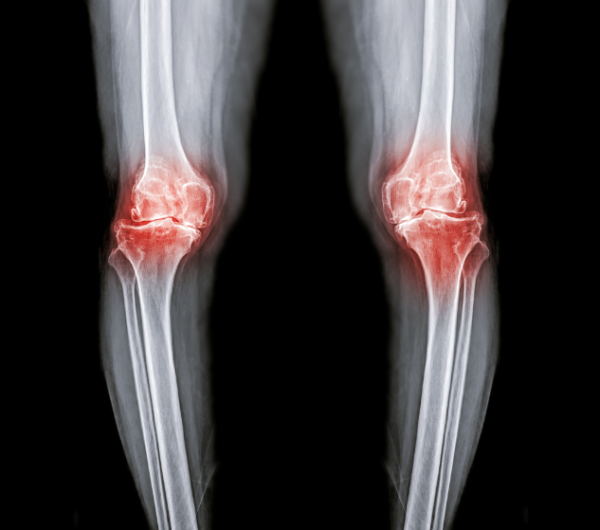

綜合內地傳媒報道,杭州市第一人民醫院皮膚性病科醫生鄧琳分享了一宗病例:一名28歲女子因盲目追求皮膚白皙,無論任何季節出門都必定撐傘,每天塗抹防曬產品高達5至6次。加上她日常飲食不規律,導致體內嚴重缺乏維他命D,最終患上軟骨病(俗稱「佝僂病」),病情嚴重至連咀嚼也頓感乏力。

(示意圖)